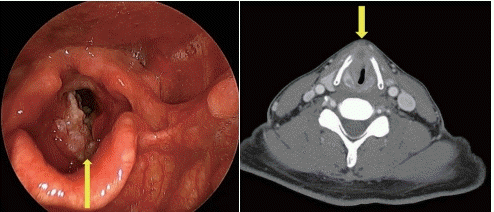

6개월 전부터 목소리가 변했고 한 달 전부터 숨이 차다고 하는 50세 남자 환자가 내원하였다. 흡연은 하루 반 갑을 30년 동안 해왔다고 한다. 후두 내시경 소견과 경부 CT 소견은 다음과 같았다. 이 질환에 대한 설명으로 맞는 것을 고르시오.

해 설 ① 우선 굴곡형 내시경을 이용해서 외래 조직 검사를 시행하고 어려울 경우 전신마취하에서 조직 검사를 시행한다. ② 다른 염증성 질환이나 양성 질환이 배제되지 않은 상태에서 치료로 들어가는 것은 바람직하지 않다. ③ 기도가 충분해 보이더라 고 전신마취 유도 시에 호흡곤란이 올 수 있고, 항암 치료나 방사선 치료 중에도 호흡곤란이 올 수 있으므로 기도 유지에 신경써야 하고 필요 시 기관절개 수술을 적절한 시점에 시행해야 한다. ④ 종양의 갑상연골의 침투로 T4a로 생각되지만 항 암방사선 치료를 초치료로 선택하고 필요 시 후두전절제 수술은 구제 수술로 시행 가능하다. ⑤ 방사선 치료만으로는 충분 한 치료 효과를 기대할 수 없고 동시항암방사선 치료나 후두전절제 수술이 필요하다.